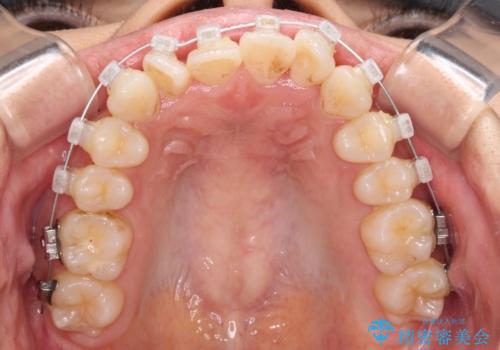

捻れた前歯をできるだけ短期間で 表側のワイヤー矯正

- クリアブラケット

- 上下前歯のねじれを気にして来院された患者様です。

ワイヤー矯正でもマウスピース矯正でも対応可能でしたが、マウスピース矯正の自己管理が面倒であること、上顎前歯の捻転が著しいことから、ワイヤー矯正での治療を希望されました。

日々前歯の捻れが解消されていくので、歯の動きを楽しみながら矯正治療を進めることができました。